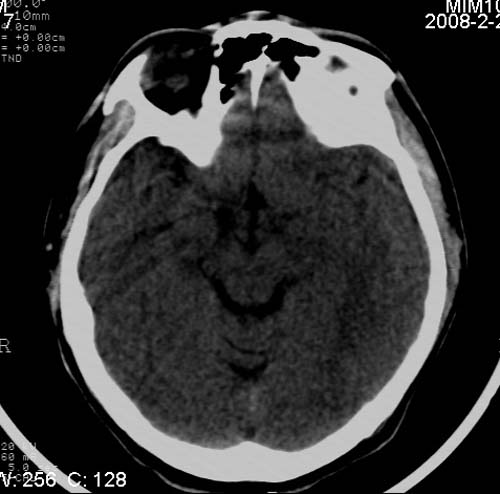

男,17岁,3天前与人斗殴,自述头痛、头晕。无恶心、呕吐,无阳性体征,一般情况良好。

其内似可见脂肪密度影,考虑畸胎瘤可能性大.

病灶以钙化为主,无明显占位效应,病灶周围无水肿,这种情况应该是脑血管畸形,最多见的是动静脉畸形,其次是海绵状血管瘤.

病人较年轻,有头疼、头晕症状,动静脉畸形可能性大。